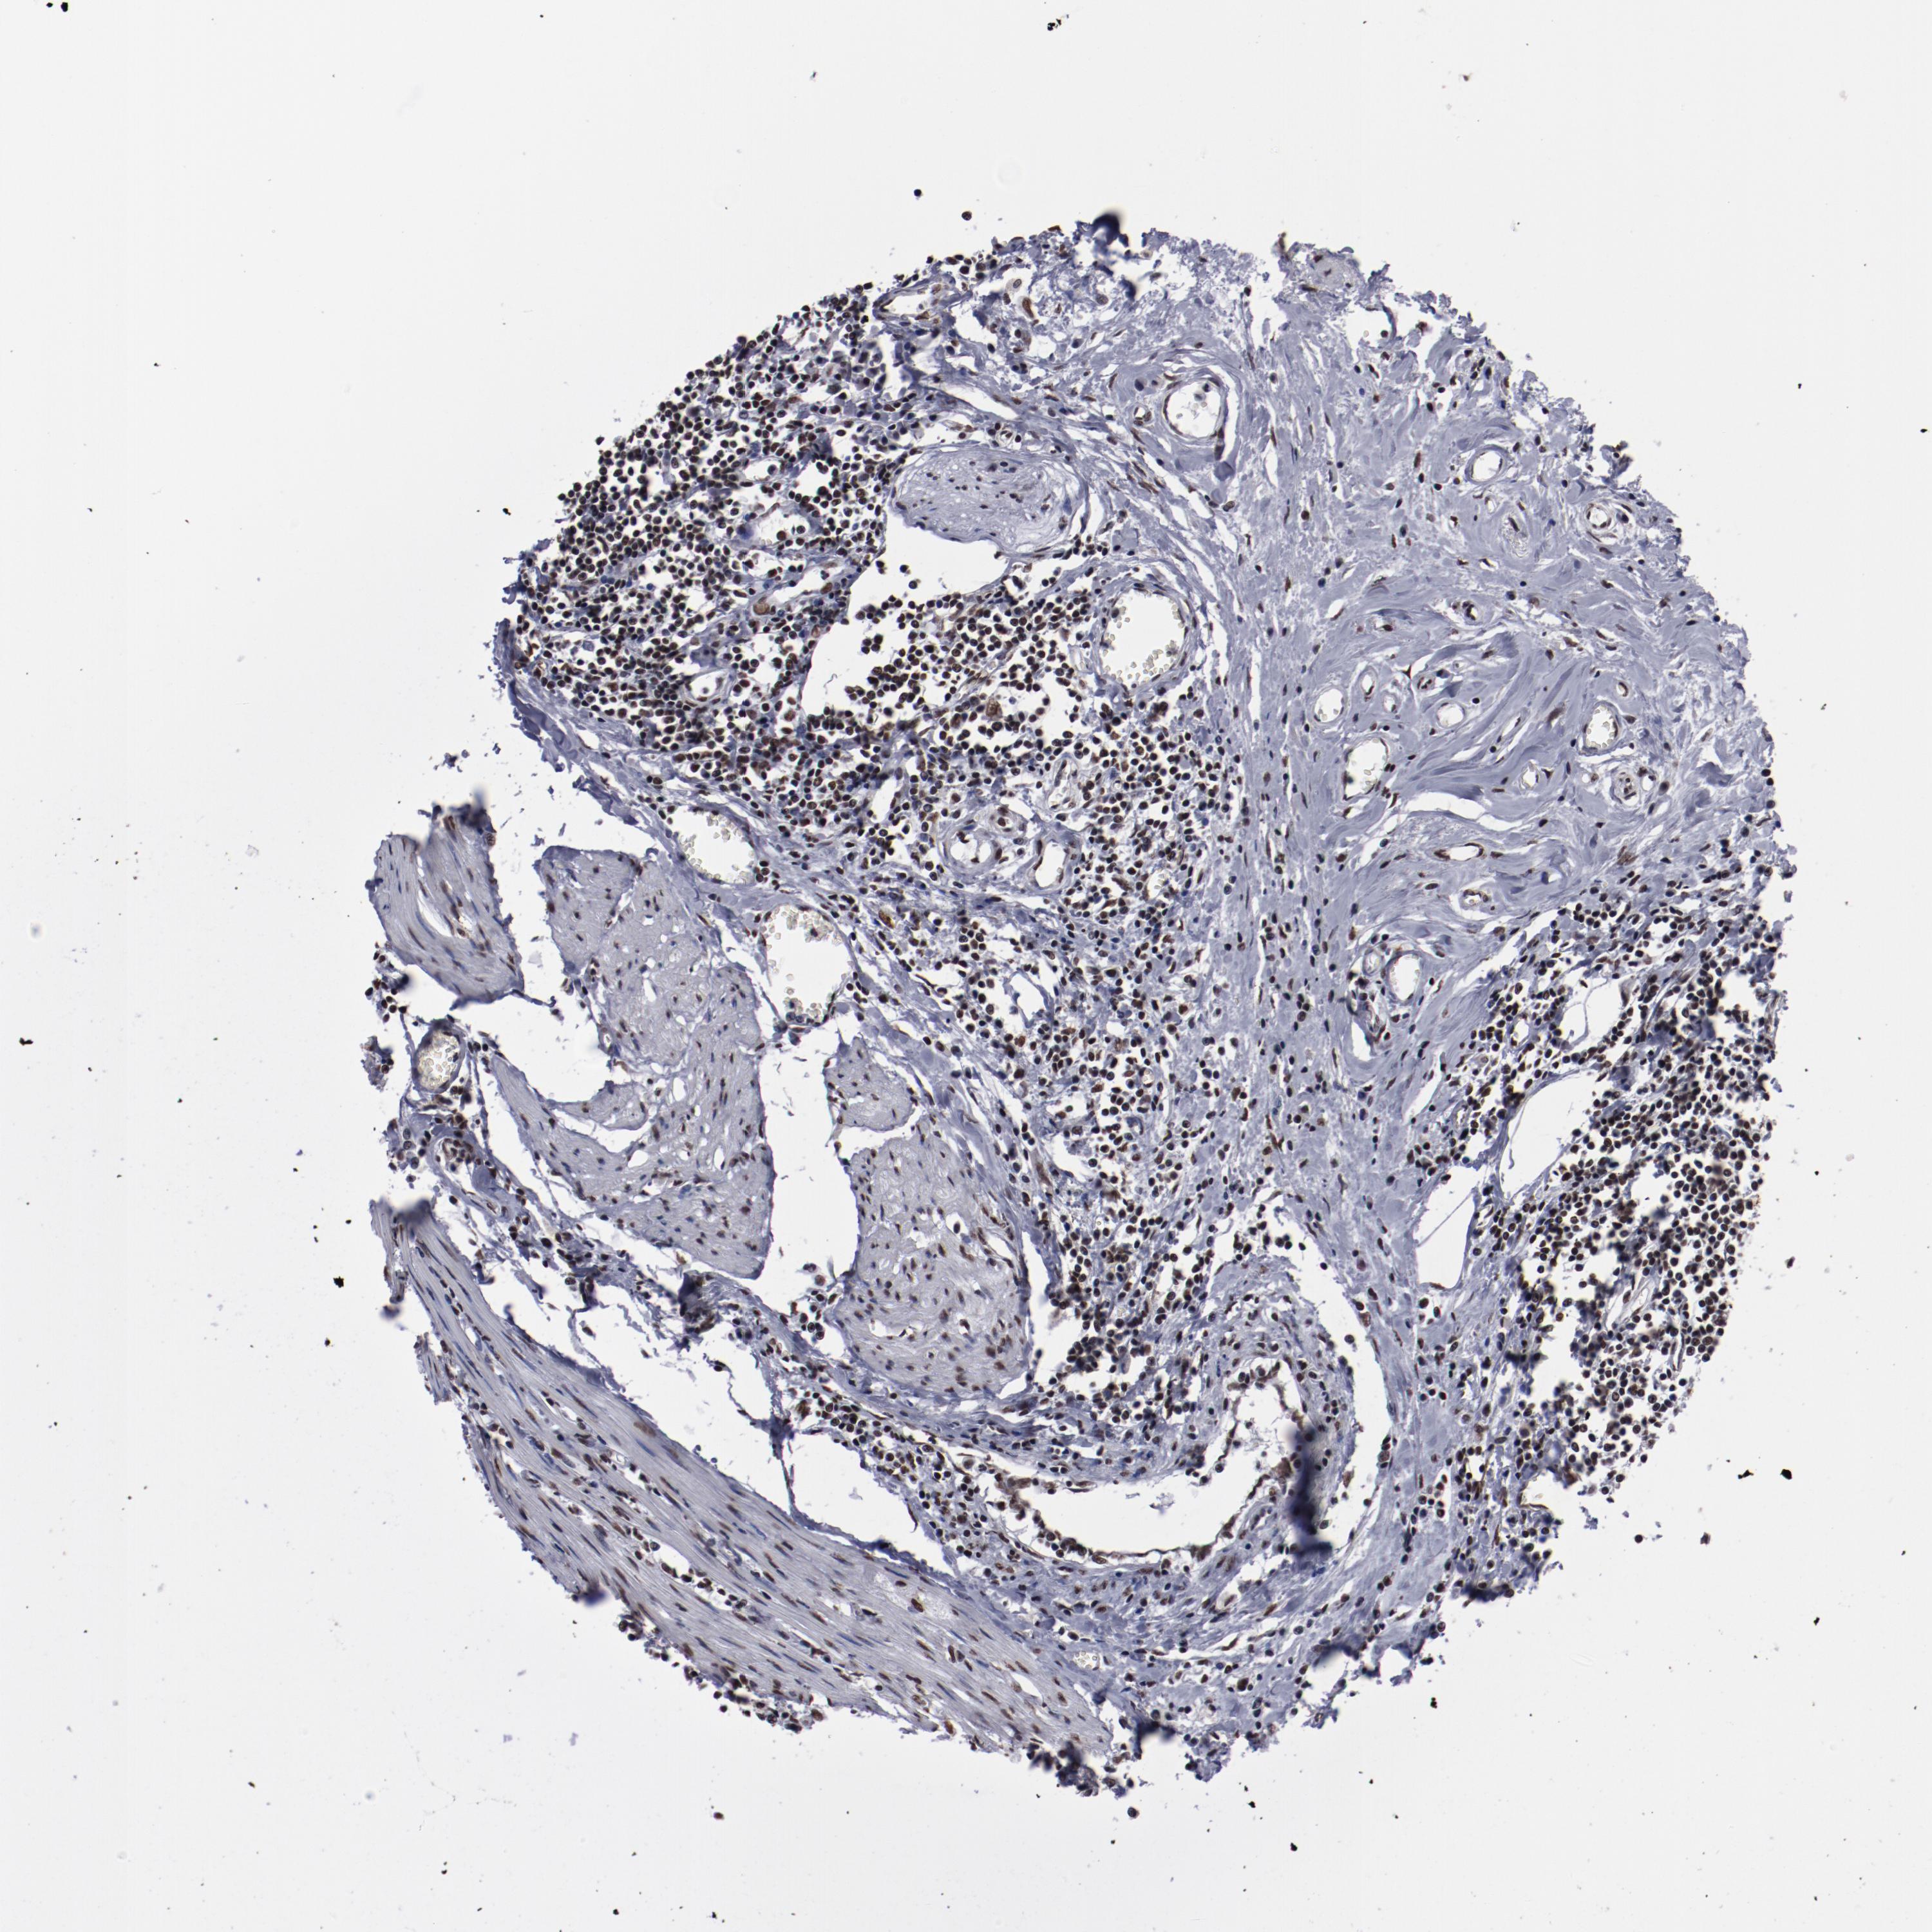

UROTHELIAL CANCER - Protein expressioni

A mouse-over function shows sample information and annotation data. Click on an image to view it in a full screen mode. Samples can be filtered based on level of antibody staining by selecting one or several of the following categories: high, medium, low and not detected. The assay and annotation is described here.

Note that samples used for immunohistochemistry by the Human Protein Atlas do not correspond to samples in the TCGA dataset.

Antibody stainingi

Antibody staining in the annotated cell types in the current human tissue is reported as not detected, low, medium, or high, based on conventional immunohistochemistry profiling in selected tissues. This score is based on the combination of the staining intensity and fraction of stained cells.

Each image is clickable and will lead to virtual microscopy that enables deeper exploration of all samples and also displays staining intensity scores, fraction scores and subcellular localization as well as patient and tissue information for each sample.

Antibody HPA001666

Antibody CAB012403

Staining

High

Medium

Low

Not detected

Intensity

Strong

Moderate

Weak

Negative

Quantity

>75%

75%-25%

<25%

None

Location

Nuclear

Cytoplasmic/membranous

Cytoplasmic/membranous,nuclear

Urothelial carcinoma, High grade

Urothelial carcinoma, Low grade

Adenocarcinoma, NOS